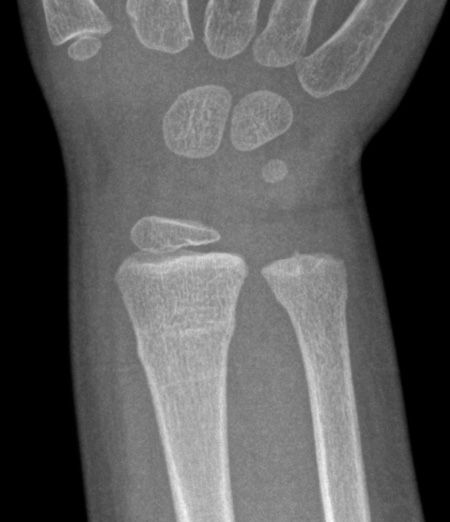

TRAUMA X-RAY 72: Injury to hand in a child. What is the eponymous fracture? Answer https://t.co/cedJdlFoPp